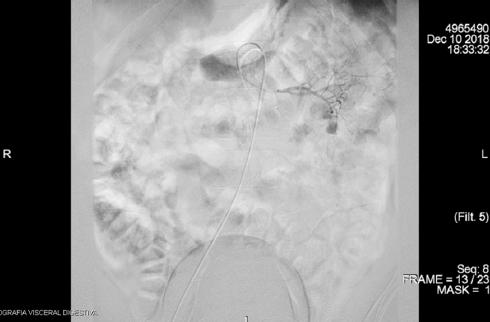

Ante la persistencia de las rectorragias abundantes que comprometían la estabilidad hemodinámica del paciente (120 latidos por minuto, 80/40 mmHg) y que requirieron la transfusión de 11 concentrados de hematíes, se realizó una angiografía por tomografía computarizada (Figs. 1 y 2), que mostró signos de sangrado activo en una lesión tumoral en el yeyuno medio. Se realizó embolización de la arteria dependiente de la arteria yeyunal por parte de radiología intervencionista (Fig. 3), inicialmente con éxito, y el paciente pasó a la unidad de reanimación posquirúrgica, sin precisar fármacos vasoactivos en ningún momento.

Figura 3 Arteriografía en la que se observa un sangrado arterial agudo de alto flujo en topografía yeyunal.